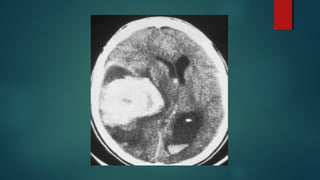

Este documento es el programa para un taller de imágenes del curso de emergencia 2015 impartido por el Dr. Víctor Delgado. El taller se centra en el uso de imágenes médicas para el diagnóstico y tratamiento de pacientes en coma traumático según la base de datos de Marshall. El Dr. Delgado es el único instructor repetido a lo largo del documento.